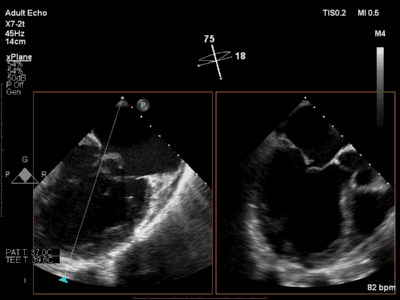

患者术前心超显示心脏扩大,严重脱垂